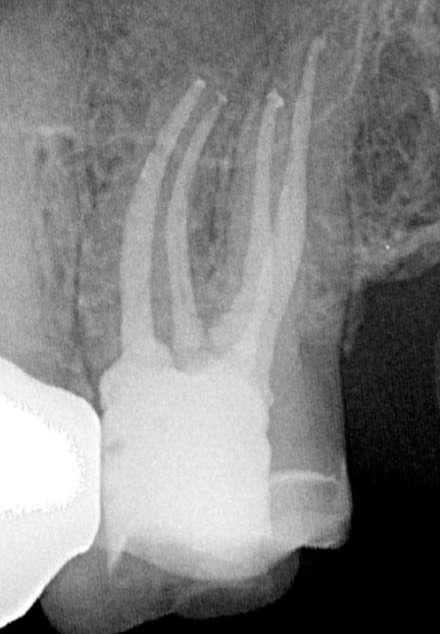

Das präoperativ angefertigte diagnostische Röntgenbild zeigt eine insuffiziente Amalgamfüllung im distalen Approximalraum. Die mesiale Wurzel weist eine periapikale Osteolyse auf (Abbildung 1).

Die endodontische Behandlung fand in einer Sitzung statt. Nach Anästhesie und Anlegen des Kofferdams erfolgte die Entfernung der provisorischen Füllung und die initiale intrakoronale Diagnostik. Mittels Microopener konnte ein mesiobukkaler, mesiolingualer, distobukkaler und distolingualer Wurzelkanal sondiert werden. Die Ausarbeitung der primären Zugangskavität zur besseren Zugänglichkeit der Kanäle erfolgte mit Langschaftrosenbohrern. Anhand des präoperativen diagnostischen Röntgenbilds konnte die Länge der Wurzelkanäle vorläufig näherungsweise bestimmt werden. Die Kanäle wurden im weiteren Therapieverlauf kontinuierlich mit 6% NaOCl gespült. Nach Ausarbeitung der Zugangskavität folgte die koronale Erweiterung der Wurzelkanäle mit EdgeEndo X7 Feilen der Größe 17.06. Die elektrometrische Bestimmung der Kanallänge mithilfe eines Morita Root ZX Mini Apex Locators wurde mit C-Piloten der Größe 8-10 durchgeführt. Nach Festlegung der Arbeitslänge wurde der

Gleitpfad rotierend mit EdgeFile X7 der Größe 17.04 und 25.04 erweitert und final bis auf 30.04 aufbereitet (Abbildung 2).

Abbildung 1: Präoperative Diagnostische Aufnahme